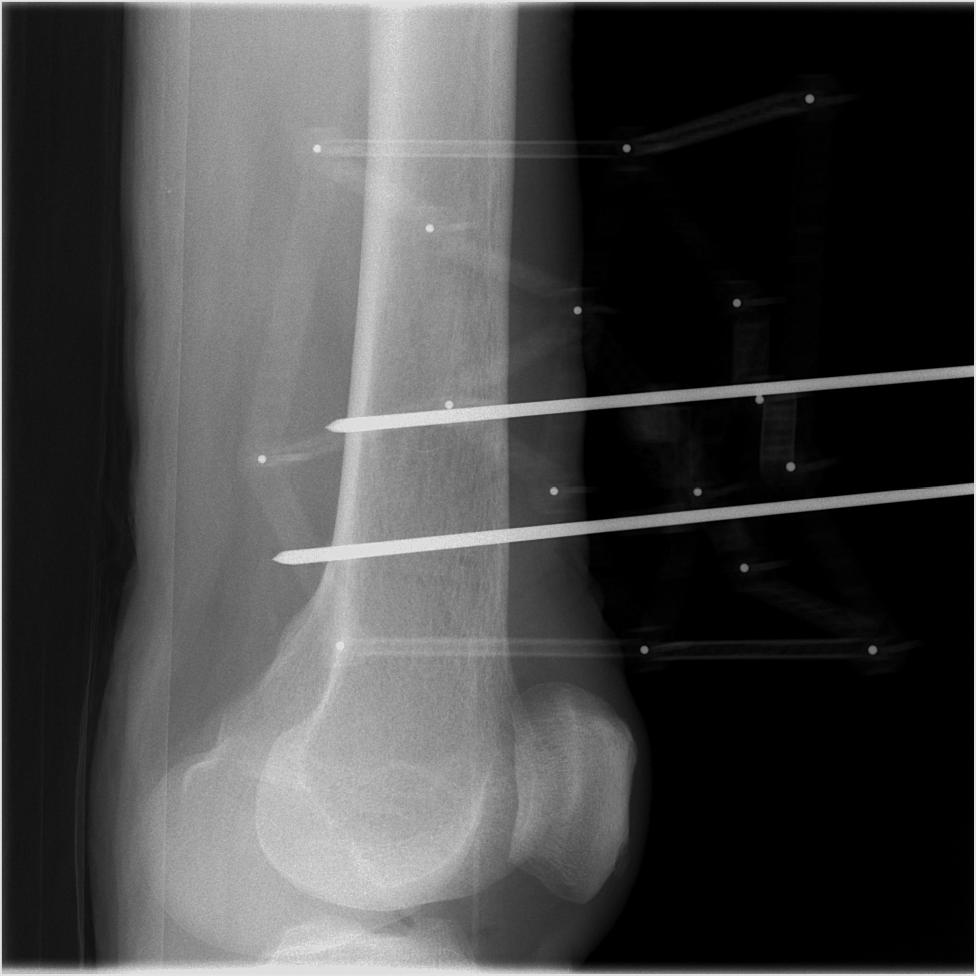

The proposed X-ray/CT calibration method is as follows. The input X-ray images are calibrated using a custom-made fiducial marker, which is attached to a 3 mm-diameter K-wire fixed to the femur. Occluding contours of the femur substructures, specifically the diaphysis and condyles, are extracted using a U-Net-based model trained on synthetic specimen-specific data. The contour segmentation process is detailed in Section 3.1. Finally, the X-ray/CT registration is solved by applying a contour-based ICP optimization to the predicted contours, as described in Section 3.2. An overview of our registration method is shown in Figure 1.

Five cadaveric distal femur specimens (three female, two male) were obtained from a certified anatomical donation program with ethical approval. Four specimens were right-sided, and one was left-sided, with a BMI range of 19–28. Additional details are provided in Online Resource 1. The CT data were acquired using the Siemens CT NAEOTOM Alpha with a resolution of 512512px and a slice thickness of 0.2mm. The X-ray images were acquired using a Siemens XA - Fluorospot Compact S1 with a resolution of 976976px and a sensor size of 296.7296.7mm. During image acquisition, the specimens were placed on a radiolucent table, while the fiducial remained fixed relative to the bone throughout X-ray imaging. The images were taken from 10 perspectives per specimen, with the C-arm rotated around the specimen at approximately 9-degree intervals. X-ray image poses were estimated using our fiducial marker.

A prerequisite to multi-view X-ray/CT registration is C-arm calibration, which refers to the computation of the relative poses of the X-ray images. Our C-arm calibration is achieved using a fiducial marker, similar to prior works [24, 10]. This approach offers a simple, effective, and accurate solution to this problem. We utilize a custom-designed fiducial marker, which is mounted on a K-wire attached to the femur at the start of the surgery. After the X-ray images are acquired, the marker can be removed. This procedure also offers the possibility of extending the registration system to optical or EMT-based tracking systems [25], which can be calibrated with the phantom prior to the surgery. For procedures like osteotomies, where a K-wire is already placed on the bone, our method only minimally deviates from the standard clinical workflow.